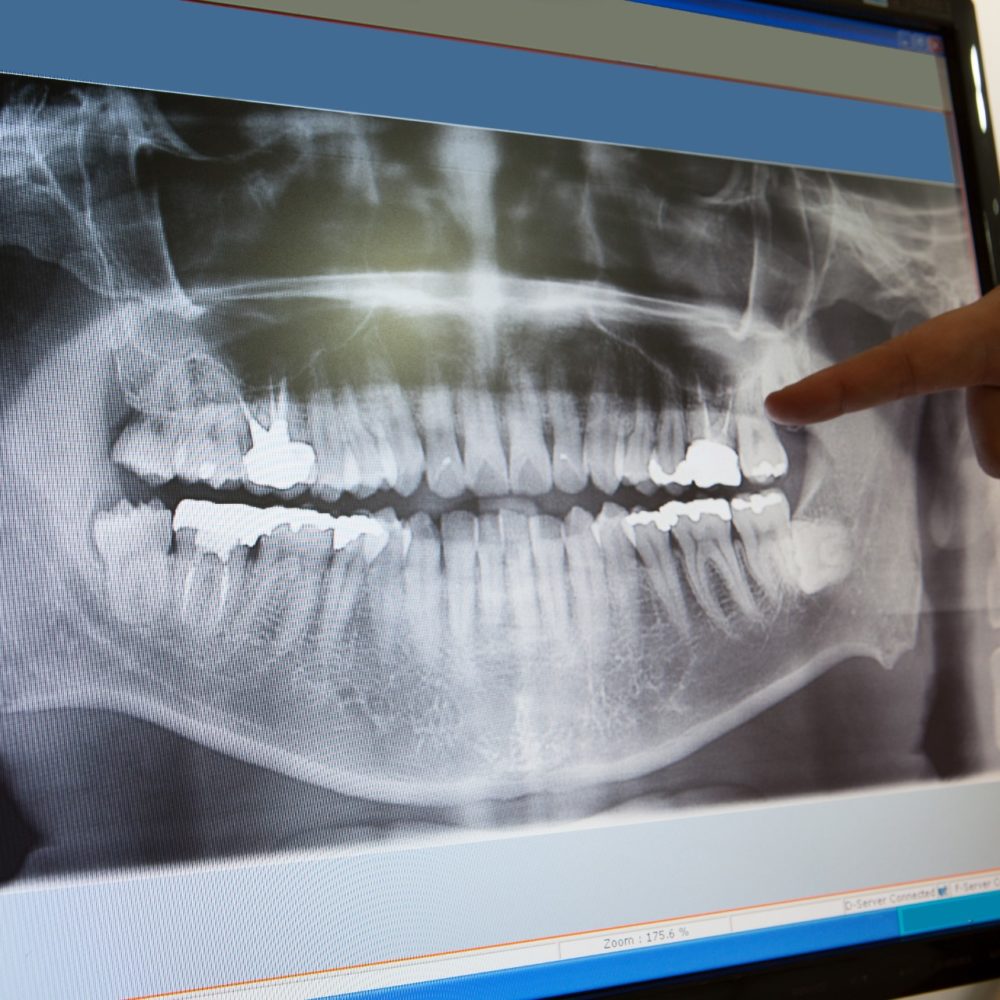

Understanding You and Your Goals

Time is created for Dr. Andersen to perform a comprehensive exam of your overall oral health. Dr. Andersen will review your historical treatment records and X-rays. She will also take photographs that will assist in the creation of dental models of your teeth. Dr. Andersen will then listen to your needs, wishes and goals regarding what you hope to see and experience when your smile is complete.